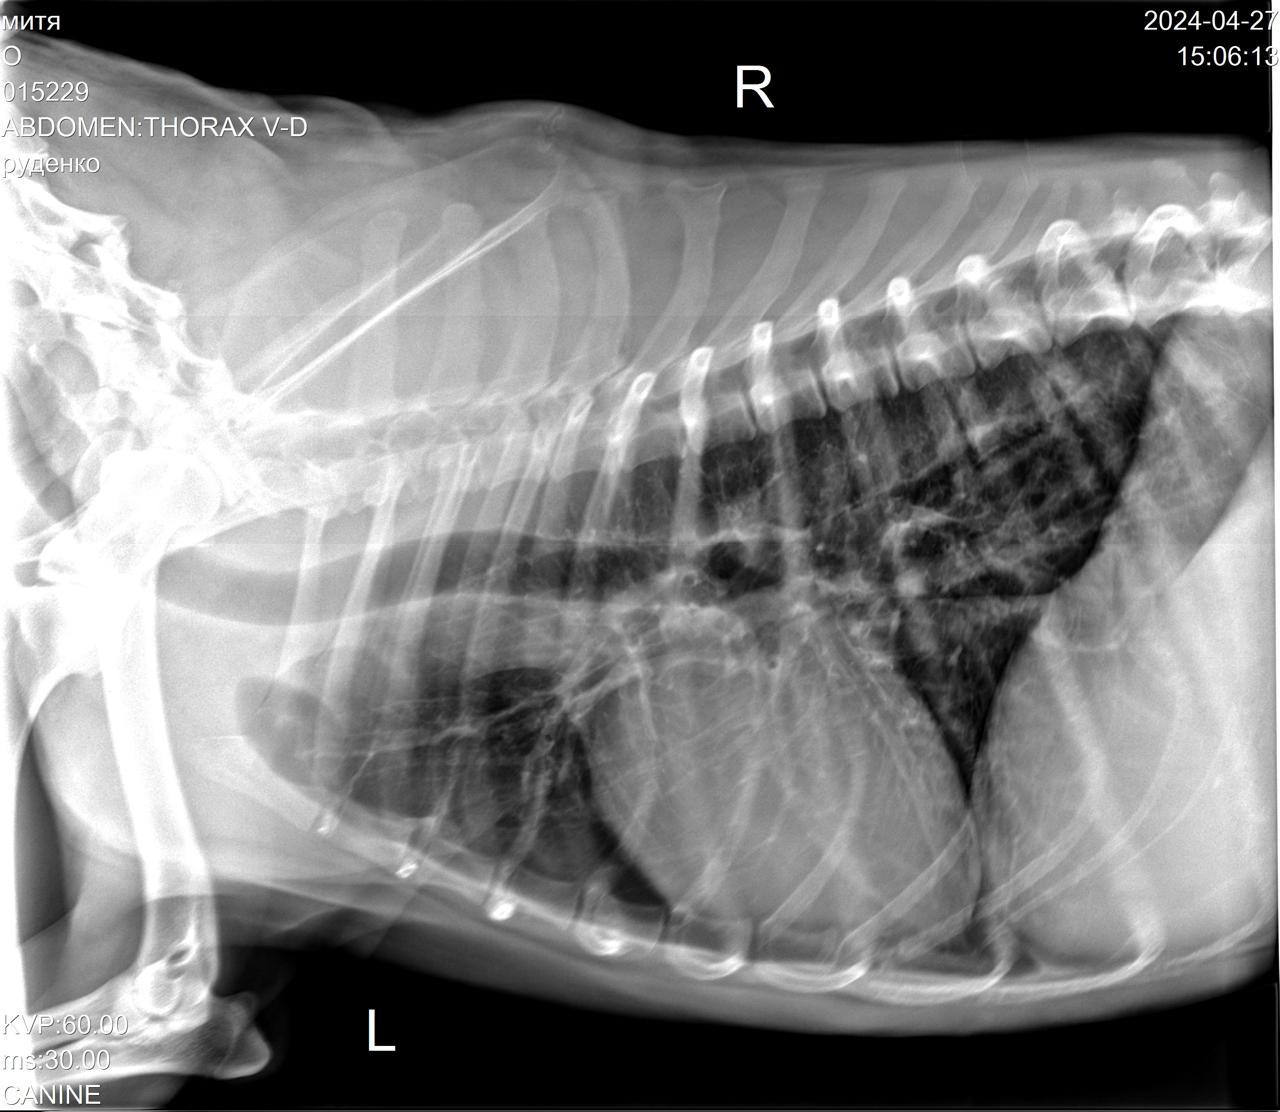

Сегодня Катюша возила Митю на рентген.

Вложения

IMG-20240427-WA0028.jpg

IMG-20240427-WA0029.jpg

IMG-20240427-WA0030.jpg

IMG-20240427-WA0031.jpg

IMG-20240427-WA0032.jpg